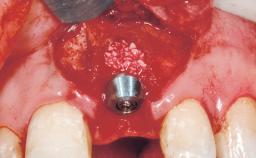

A 30-year-old female patient was referred to the office for the treatment of tooth 11. Her chief concern at the initial visit was to inquire, “Why is my tooth pink?” Upon clinical examination, it was determined that tooth 11 had a previous history of trauma and that the clinical crown had become noticeably pink in color as a result of internal resorption. This diagnosis was confirmed radiographically, indicating a large radiolucency involving the central and distal portions of the clinical crown. It was determined that restoration of this tooth was not possible, and that extraction was indicated. The presence of a mid-line diastema, which the patient wanted to reproduce, directed the treatment plan for tooth replacement utilizing a dental implant.

Bone Augmentation Horizontal|Simultaneous

Augmentation Materials Autogenous chips|Membrane

Placement Protocol Immediate implant placement

Socket Integrity Sufficient, with intact bone walls

Bone Volume Sufficient, with intact walls